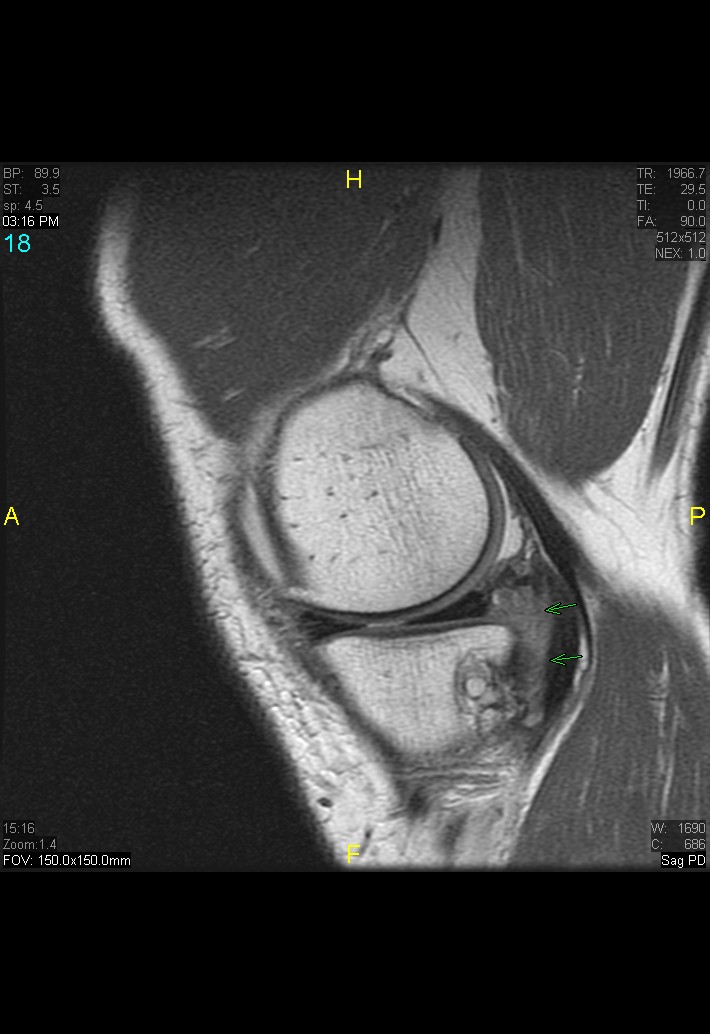

Figure 3 for case gout arthritis ( RID3567 )

Figure 3